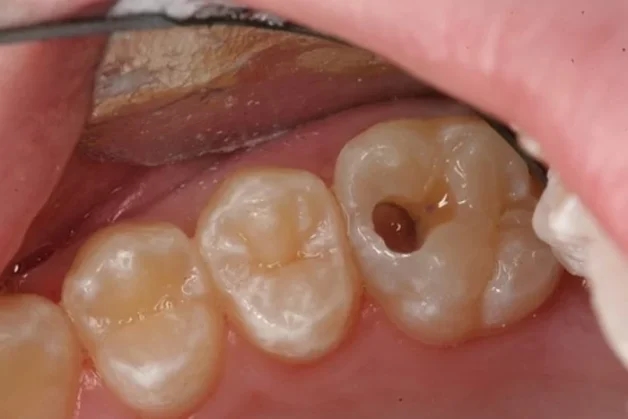

Khi sâu răng nặng sẽ hình thành các lỗ sâu lớn, gây ảnh hưởng đến tủy răng

Sâu tủy răng là vấn đề bắt nguồn từ việc sâu răng kéo dài mà không được chữa trị. Khi tình trạng răng bị ăn mòn do vi khuẩn tạo thành các lỗ sâu mà không được điều trị, các lớp thành phần cứng của răng như men răng, ngà răng sẽ bị phá hủy nhiều hơn, vi khuẩn ăn sâu vào đến buồng tủy, tấn công tủy răng gây ra tình trạng viêm nhiễm, hay chúng ra còn gọi nôm na là sâu tủy răng.